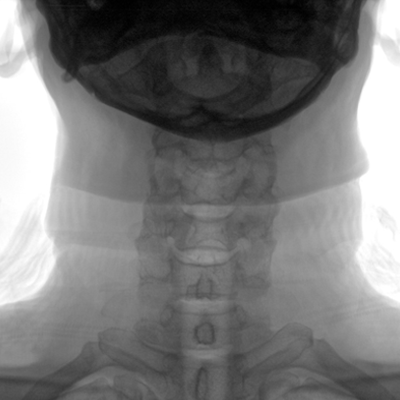

大尺寸動態(tài)平板探測器,高DQE、低噪聲、圖像清晰。采用多分辨率圖像增強(qiáng)處理技術(shù),不同部位不同圖像處理算法,滿足客戶多樣化的需求。

采用智能變頻脈沖透視技術(shù),優(yōu)化圖像質(zhì)量的同時降低輻射劑量,呵護(hù)醫(yī)患健康